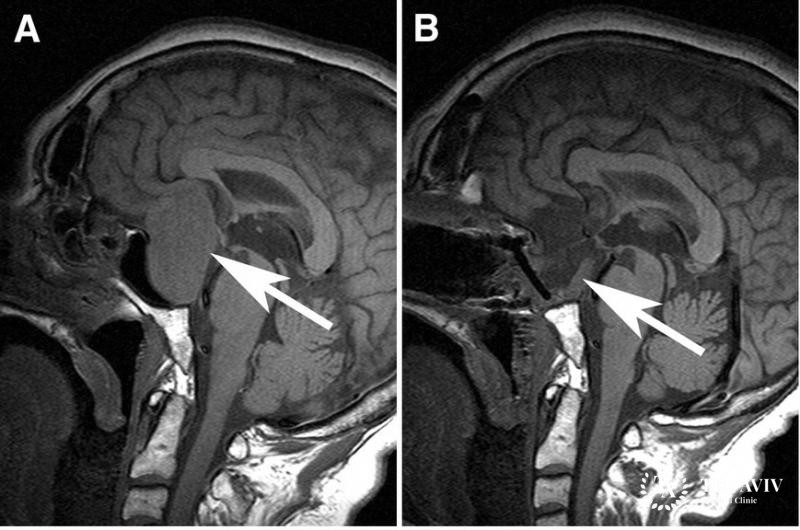

Гонадотропиномы – разновидность аденом гипофиза, относящаяся к доброкачественным новообразованиям в области головного мозга. Зона дислокации – передняя часть гипофиза. В основе развития патологии клетки, производящие гормон гонадотроф. При формировании гонадотропиномы выработка лютеинизирующих, фолликулостимулирующих гормонов повышается. Гормоны взаимодействуют с половыми, стероидными гормонами в ходе биосинтеза.

- Резекция гонадотропиномы. Операция признана результативным методом с максимальной инвазией. Для проведения процедуры врач использует носовой ход. При недоступности опухоли через нос, вскрывается черепная коробка.